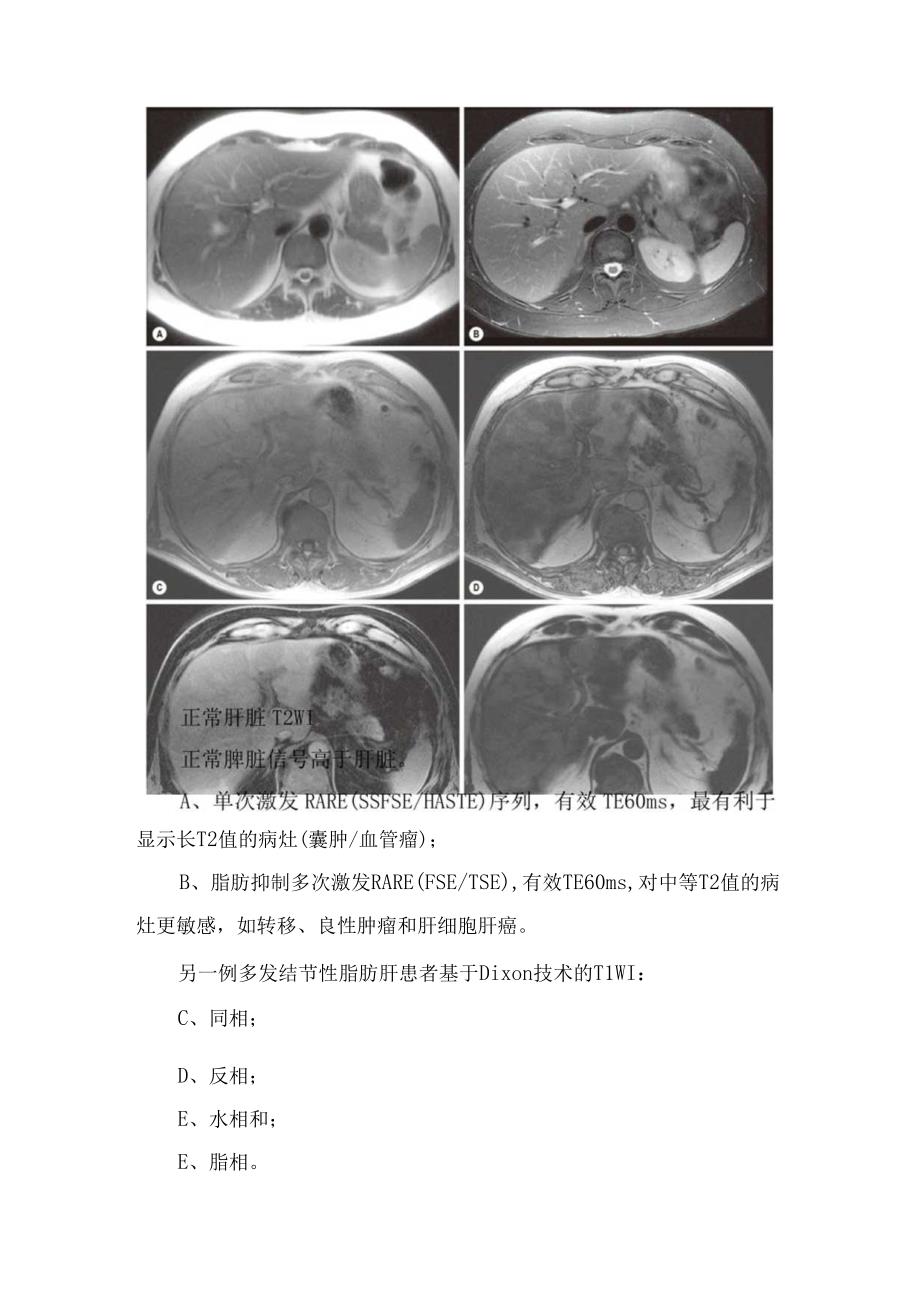

2、,肝脏回声异常增加CT能显示和量化弥漫性脂肪肝,每Ig肝实质中的甘油三酯增加Img,肝脏密度减低约1.6HU。但同时伴发其他情况如肝纤维化、药物治疗以及血色病时,这种定量方法不可靠。肝脏解剖结构尤其是血管结构得到保留,注射造影剂后肝实质强化正常。肝脏密度随脂肪浸润的增加而减低,并使肝-脾及肝-血管之间的密度差发生反转(图)。弥漫性脂肪肝CT表现。平扫CT肝实质密度显著减低,反转与脾和血管密度的正常关系。肝脏的形状和血管结构正常MRI是显示脂肪肝最敏感和最具特异性的技术,基于Dixon技术(图)的“化学位移”或“同反相位”成像(图),通过合适的T2设置及其他校正方法,可以实现准确诊断和定量。MR

3、l也是诊断局灶性脂肪含量改变最准确的检查方法。显示长T2值的病灶(囊肿/血管瘤);B、脂肪抑制多次激发RARE(FSE/TSE),有效TE60ms,对中等T2值的病灶更敏感,如转移、良性肿瘤和肝细胞肝癌。另一例多发结节性脂肪肝患者基于Dixon技术的T1WI:C、同相;D、反相;E、水相和;E、脂相。现代技术允许单次呼吸3DT1WI扫描同时产生4种图像。反相位信号降低提示同一像素内同时存在水和脂肪。弥漫性脂肪肝MRI化学位移或同相(八)和反相(B)梯度回波成像。由于同一体素内存在水和脂肪时其信号相互抵消,脂肪的存在会导致信号显著降低(B)。肝脏的脂肪化程度存在一定的空间差异。肝硬化肝硬化是一系